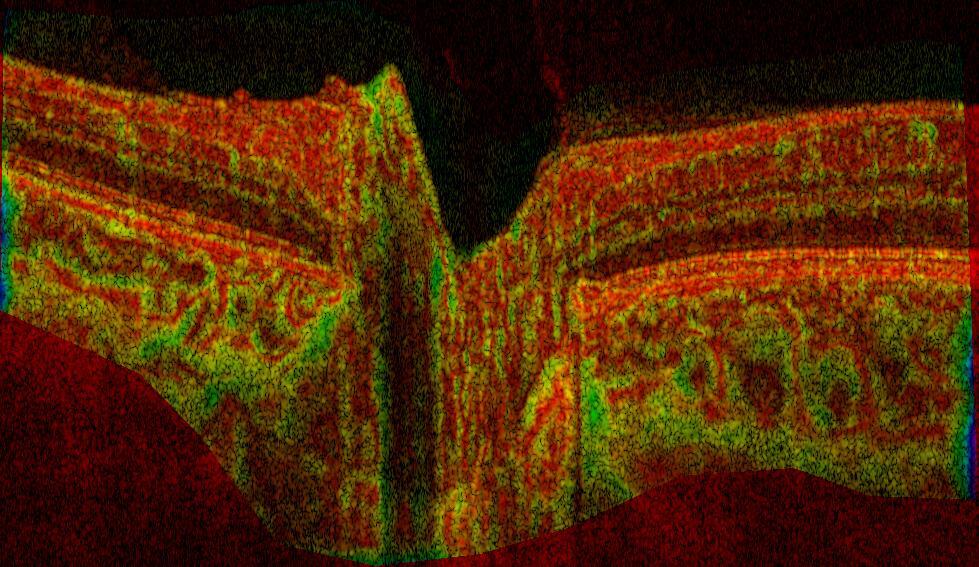

The biomechanics of ocular tissues plays a central role in the development of blinding diseases. We develop image processing techniques to diagnose and understand the pathophysiology of ophthalmological conditions.